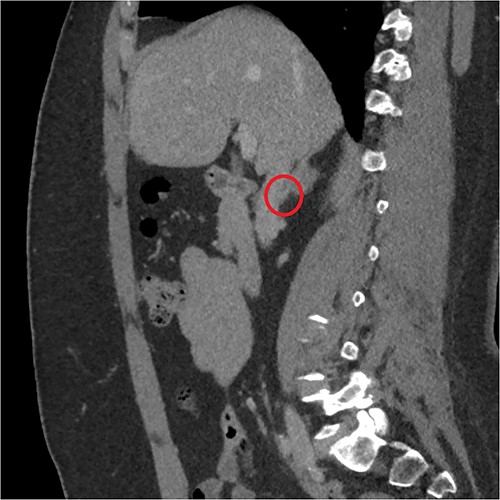

The endocrinological study showed a hypersecretion of cortisol with suppressed ACTH (550 mcg/l, ACTH 1.1 ng/ml, urinary free cortisol 255 mcg/24 h, positive overnight Nugent test). The serum concentration of renin and aldosterone and the urinary concentration of metanephrine are instead normal. Therefore, the patient underwent an abdominal CT scan that showed a right adrenal lesion of about 7 cm with an adenomatous appearance (Fig. 1). The saggital 3D reconstruction of CT scan in venous phase had raised the suspicion of short course of the adrenal vein in the lower lateral lip of the mass (Fig. 2). To better define the relationship between the neoplasm and the inferior vena cava, the vascularization of the adrenal gland with any anatomical anomalies and the specific location of the middle adrenal vein, a 3D printed model was created in 1:1 size based on the preoperative CT scan.

Sagittal 3D reconstruction of CT scan in venous phase. In particular, the images had raised the suspicion of the short course of the adrenal vein in the lower lateral lip of the mass.